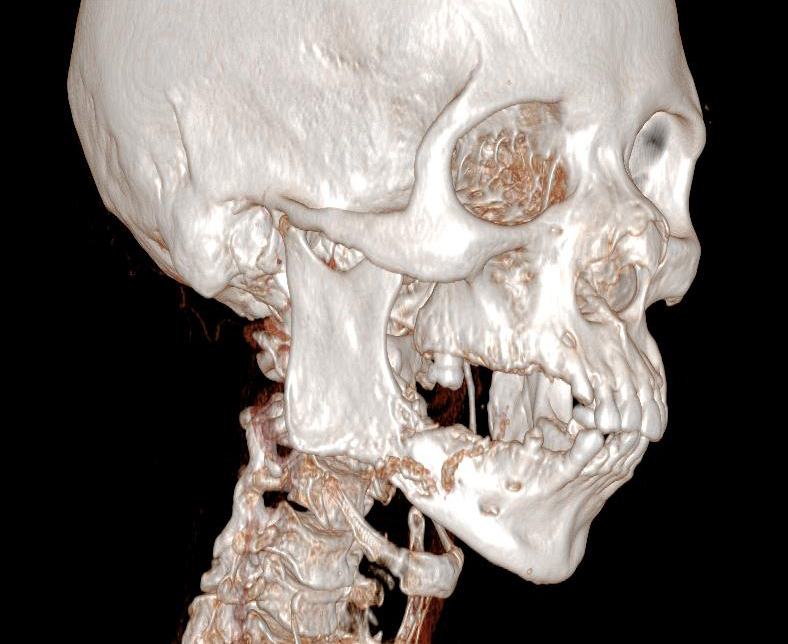

À rechercher devant toute pathologie de la région parotidienne. Un testing musculaire doit être réalisé. Sa présence oriente vers la malignité.

En cas de tumeur maligne, il peut exister des ganglions cervicaux.